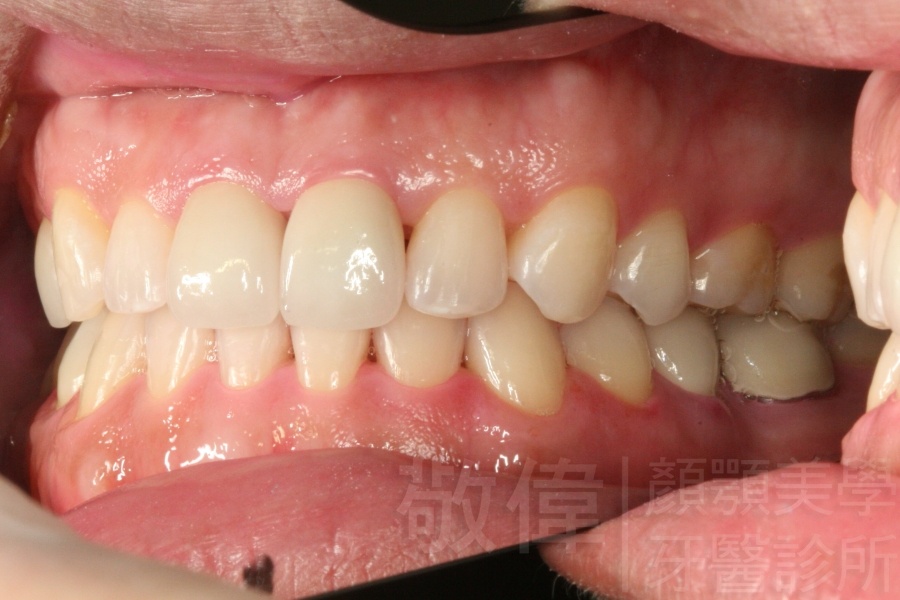

齒顏矯正/變臉矯正-月亮妹 變身 陽光正妹

變臉矯正,原來戽斗妹跟大歪臉變成自信正妹

因為矯正與正顎手術的配合,使「戽斗妹」變成了「陽光正妹」,完全的改變了她的人生,在面對各種場合、與人交際都散發出自信微笑。所以,奉勸家長,如果小朋友有臉顎畸型的問題,應該考慮配合做這種簡單、安全、有效的正顎手術。

「3D齒顎顏矯正」,不止矯正您的牙齒,也會改變您的人生。「治療前」和「治療後」出社會的人生際遇一定會截然不同。